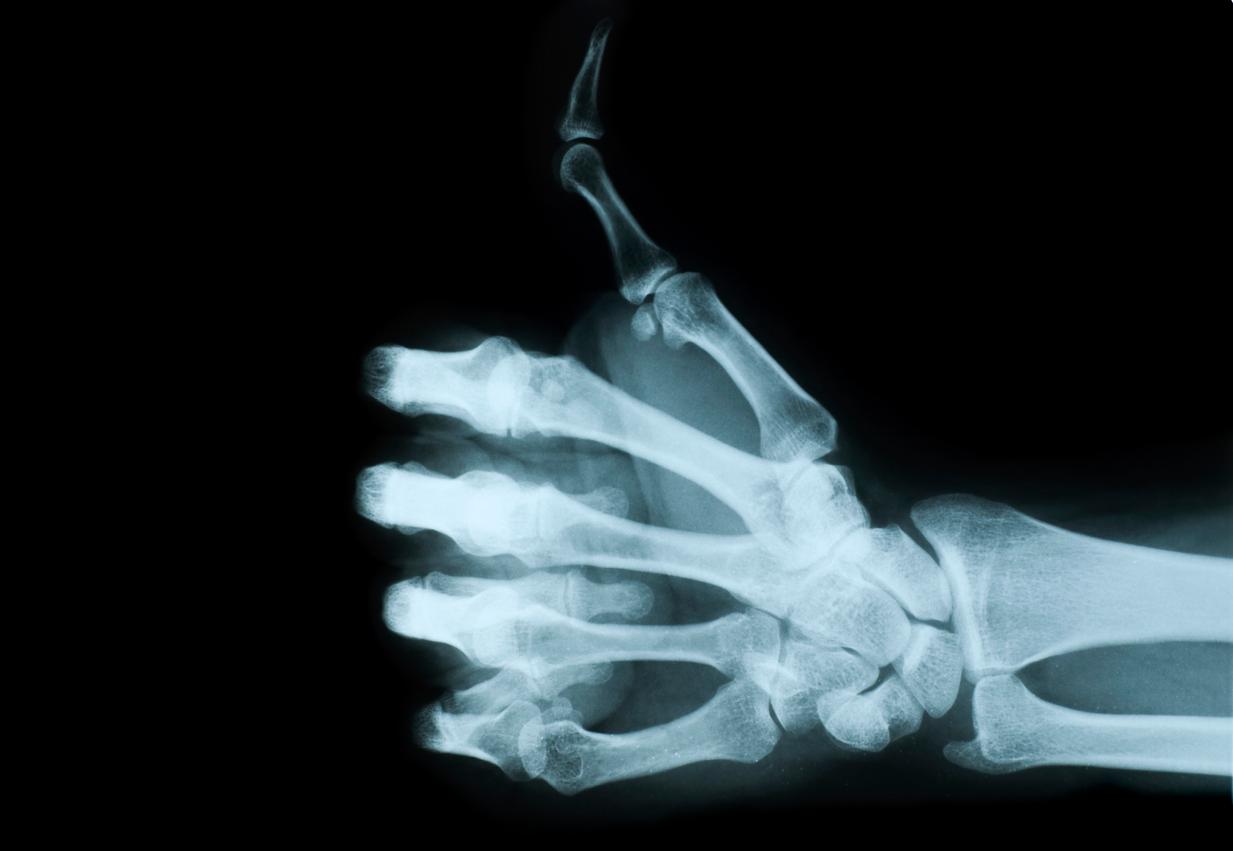

FRAGILITY FRACTURES

Osteoporosis is clinically significant because of the occurrence of fragility fractures, which result from mechanical forces that would not ordinarily result in fracture, known as low-level (or ‘low energy’) trauma, equivalent to a fall from a standing height or less.2 The most common sites for fragility fracture are the spine (vertebrae), wrist (distal radius), and hip (proximal femur) although they may occur in the ribs, pelvis and other bones. Low bone density is a major risk factor for fragility fracture.